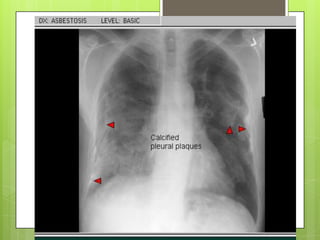

RADIOGRAFÍA Y ESPIROMETRÍA

 Imágenes lineales en campos inferiores y

engrosamiento de pleura parietal 

calcifican (>20 años)

RADIOGRAFÍA Y ESPIROMETRÍA Imágenes lineales en campos inferiores y engrosamiento de pleura parietal  calcifican (>20 años)  Altera precozmente la espirometría: patrón restrictivo REALCION VEF1 /CVF normal o aumentada